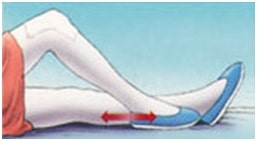

پمپ های مچ پا

با انقباض عضله ساق پا و عضلات ران به صورت ریتمیک پای خود را بالا و پایین ببرید. این حرکت را به صورت دوره ای دو تا سه مرتبه در روز و هر بار به مدت دو تا سه دقیقه در اتاق ریکاوری انجام دهید.

این حرکت را ادامه دهید تا بطور کامل بهبودی پیدا کنید و ورم مج پا و قسمت پایین پا به طور کامل از بین برود.